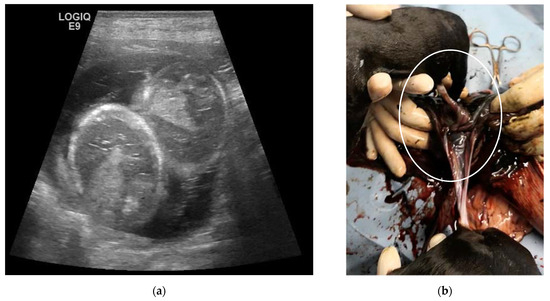

| 4C | 5-year-old Labrador Retriever female dog | 25, 32, 39, 46 and 53 | 10 | Monochorionic twins, morphologically comparable to the other embryos/foetuses. | C-section. Twins of different sex, alive, with partial twisting of the umbilical cord. One stillborn, two puppies euthanatized for malformations. | Death of the male twin after 7 days of hypoglycaemia and dehydration. |

| 5C | 3-year-old Australian Shepherd female dog | 23, 30, 37, 44 and 51 | 12 | Monochorionic twins, morphologically comparable to the other embryos/foetuses. | Natural delivery, dystocia, C-section. Ten puppies alive and two dead twins of the opposite sex. | |

| 6C | 5-year-old Rottweiler female dog | 45 and 55 | 4 | Monochorionic twins, morphologically comparable to the other foetuses; foetal death of the twins. | Natural delivery of two puppies, C-section, and extraction of the twins. | |

| 7C | 3-year-old Golden Retriever female dog | 50 | 14 | Monochorionic twins, morphologically comparable to the other foetuses. | C-section. Twins alive and of opposite sex, slightly dysmature. |